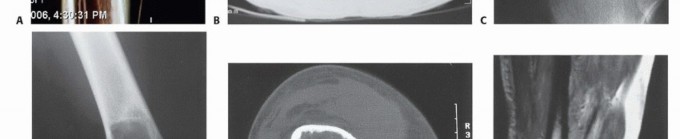

Radiographic and Advanced Imaging Modalities

- Plain Radiography: The cornerstone of initial evaluation. It accurately predicts the diagnosis in over 80% of extremity bone tumors. It defines the lesion's location, zone of transition (narrow/sclerotic = benign/slow; wide/permeative = malignant/aggressive), cortical destruction, and periosteal reactions (Codman triangle, onion-skinning, sunburst pattern).

- Computed Tomography (CT): The modality of choice for assessing fine osseous detail, cortical integrity, and matrix mineralization. Thin-slice (≤1 mm) helical CT allows for precise 3D reconstructions. Intravenous contrast is essential to delineate the relationship of the soft tissue mass to major vascular bundles. Chest CT is mandatory for staging to rule out pulmonary metastases.

- Magnetic Resonance Imaging (MRI): The gold standard for evaluating the local extent of the tumor. It accurately defines the intramedullary extent (allowing calculation of bone resection levels), soft tissue extension, joint involvement, and the presence of skip metastases. T1-weighted images best define marrow replacement; T2-weighted and STIR sequences highlight peritumoral edema and the soft tissue mass. Contrast enhancement differentiates cystic from solid components and clarifies neurovascular proximity.

- PET-CT (FDG): A functional imaging modality measuring glucose metabolism. It is increasingly the standard of care for total body staging, identifying occult metastases, and monitoring the metabolic response to neoadjuvant chemotherapy (measured by the Standardized Uptake Value, SUV).